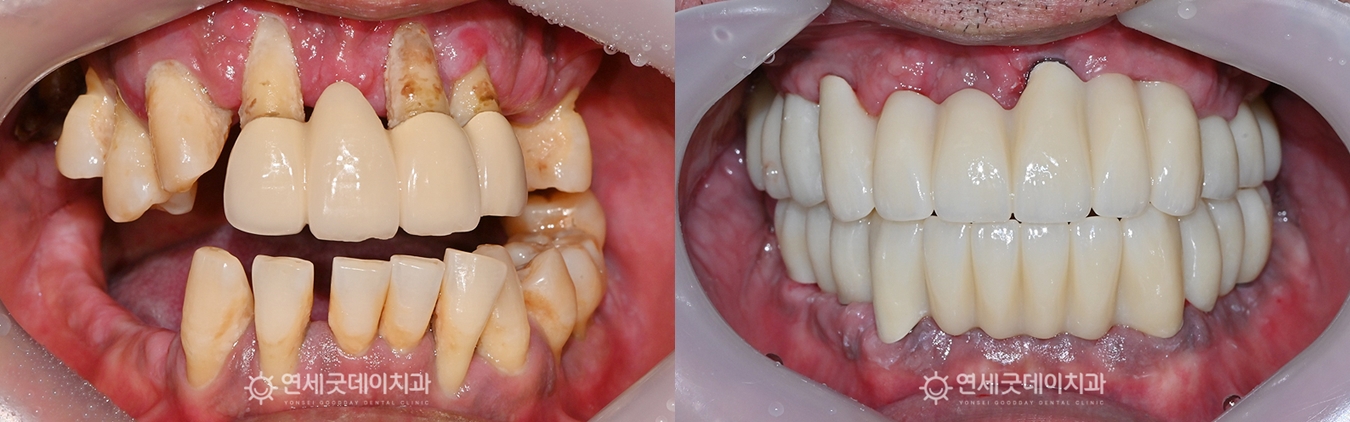

전악 브릿지 임플란트 치료전후 (50대 남성)

● 담당과 : 치주과 + 보철과 전반적인 임플란트 상담을 위해

환자분은 중등도 이상의 치주질환으로 인해 이로 인해 치아 배열이 불규칙해지고

엑스레이 상에서도 상하악 모두 이 밖에도 좌우 어금니가 상실되었고

앞니 일부는 크라운으로 수복된 상태였으며 또한 잔존치의 예후도 좋지 않았기 때문에

잔존치 발치와 동시에 임플란트 뼈이식과

수술 당일에 브릿지 임플란트 임시치아까지 환자분은 전악임플란트 치료이지만 모든 부위에

전악임플란트 치료를 마친 후의 모습입니다. 광범위하게 소실되었던 잇몸뼈는 뼈이식을 통해

특히 길어보였던 전치부 잇몸 라인을 보완하며 또한 어금니 교합도 안정적으로 형성되었으며

치료 전 모습이 떠오르지 않을 정도로

환자분은 다수의 치아 상실이 있었을 뿐만 아니라 그럼에도 환자분의 구강 상태에 맞춘 치료계획과 먼 울진에서 내원하시느라 고생 많으셨으며